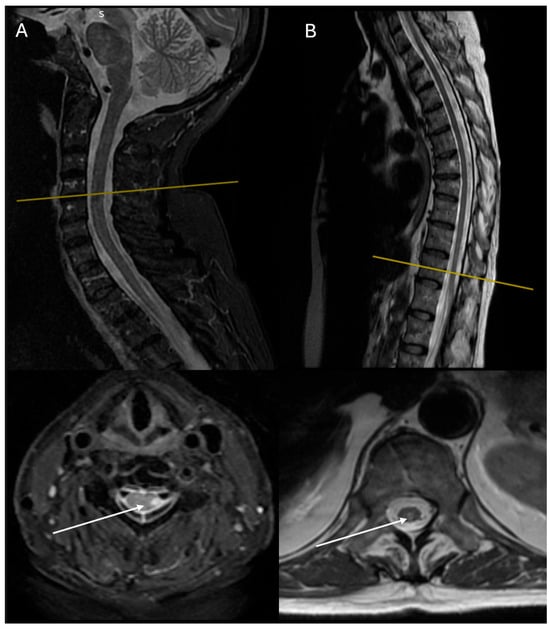

| Level | T3–T8 | T3–T8 | C3–C7 | C4–C7, T10–T12 |